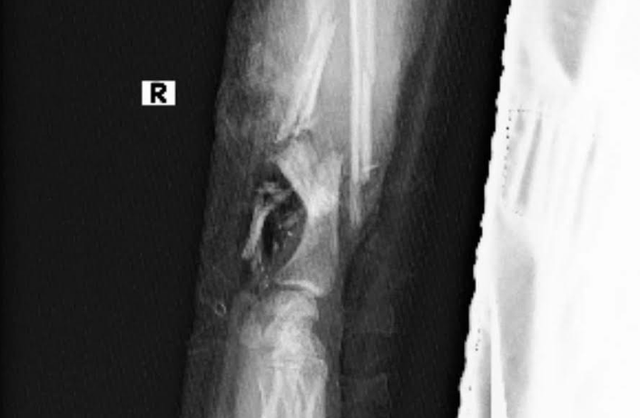

Trao đổi với phóng viên ngày 25/9, một thành viên ê-kíp phẫu thuật cho biết, khi nhập viện, bệnh nhân bị dập nát 1/3 dưới cẳng tay, bàn tay phải đứt lìa sau tai nạn lao động.

"Tổn thương ở vùng tay quá nặng, mạch máu bị dập nát, mô lại rất bẩn. Nếu nối ngay thì nguy cơ thất bại rất cao: chi sẽ bị ngắn, dễ hoại tử, nhiễm trùng nặng, thậm chí dẫn tới nhiễm trùng huyết, suy đa tạng, nguy hiểm cho cả mẹ và hai con", bác sĩ phân tích.

Một ca nối bàn tay đứt lìa thường kéo dài 7–8 giờ. Với một thai phụ song thai mới 23 tuần tuổi, thời gian gây mê lâu có thể ảnh hưởng nghiêm trọng đến thai kỳ, thậm chí gây sảy thai. Nếu chọn giải pháp tạo mỏm cụt, bệnh nhân sẽ vĩnh viễn mất bàn tay phải – đồng nghĩa không còn cơ hội tự chăm sóc con bằng đôi tay của mình.